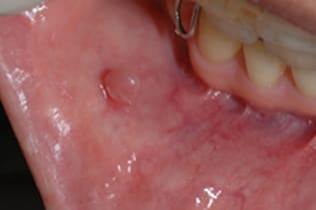

症例6 頬粘膜腫瘍(線維腫)の手術(40歳代 女性)

右側の頬にできものができ治らないので当クリニックを受診された。

右側頬粘膜に境界明瞭な弾性硬の腫瘍を認め、線維腫を疑い腫瘍摘出術を施行した。